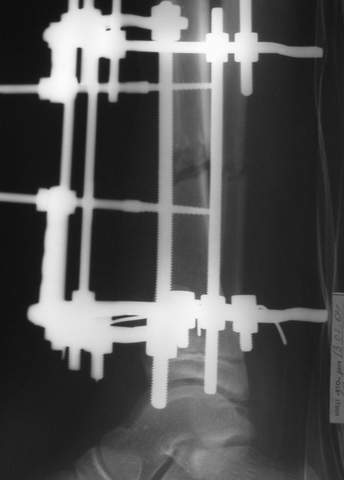

3b

В аттачте № 3 - один из примеров полукольцевого аппарат...

Это уже я баловался.

Итог? Работы больше (по времени и

интраоп "подгонке"), срастается также, а особого преимущества по сравнению с

"чиста" кольцевым (вес, удобство ношения и пр.) - я, по крайней мере,

не нашел.

Теперь не балуюсь.